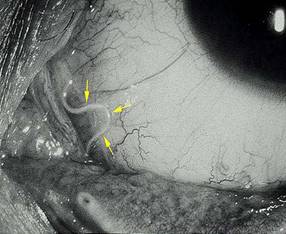

Khi nhiễm giun chỉ loại này ở mắt. Mắt sẽ bị phù, ngứa, đôi khi thấy được con giun di chuyển dưới lớp da căng phồng; túi lệ đôi lúc có thể tìm thấy giun chỉ chui vào và gây viêm túi lệ; ở kết mạc có thể thấy giun chỉ di động dưới kết mạc, có khi gây xuất huyết dưới kết mạc tái đi tái lại Riêng tại mống mắt thể mi, lúc giun chỉ chui vào thể mi sẽ gây viêm mống mắt rất nặng, đau dữ dội, tiền phòng có thể nhìn thấy giun chỉ màu trắng, di chuyển tương đối nhanh, ngoằn nghoèo, hay ở dịch kính đôi khi thấy đầu con giun chỉ cắm vào võng mạc, còn thân thì lưng lửng trong dịch kính, dịch kính vẩn đục thể hiện tình trạng viêm. Đáy mắt có biểu hiện tình trạng viêm màng bồ đào, gai thị kèm theo viêm mống mắt thể mi, có khi thấy được giun chỉ dưới võng mạc đi đôi với những đám xuất huyết và dịch tiết.

Hình 5